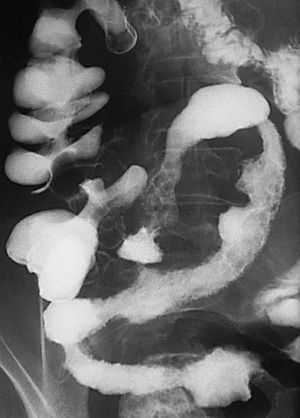

Subtipo fistulizante perforante

En este suptipo (fig. 10) hay también un proceso inflamatorio activo y aparece estriación de la grasa mesentérica en relación con edema e inflamación, pero las ulceraciones fisurantes se hacen más profundas (úlceras en "espina de rosal"). Estas ulceraciones penetrantes van a ser la base de las futuras fístulas y también de las complicaciones extraluminales, como pueden ser abscesos o masas inflamatorias.

Fig. 10.--Enfermedad de Crohn. El subtipo fistulizante-perforante se caracteriza por la presencia de ulceraciones penetrantes en el contexto de un proceso inflamatorio activo a nivel de la pared. (A) Estudio baritado que revela la existencia de ulceraciones penetrantes. (B) Correlación microscópica de una de esas ulceraciones penetrantes, con su aspecto serpinginoso y anfractuoso, irregular, rodeada por el infiltrado inflamatorio.

Para los pacientes con EC el riesgo de padecer una fístula durante su vida se sitúa entre el 20 y el 40%. En el caso de las fístulas perianales el riesgo es acumulativo y aumenta con el paso de los años: del 21% a los 10 años, al 26% después de los 20 años de enfermedad18. En el diagnóstico por imagen de las fístulas anorrectales la fistulografía está siendo reemplazada por la RM, que ha demostrado gran precisión a la hora de determinar y diferenciar los trayectos fistulosos y abscesos8,19,20. Las ventajas de la RM frente a la TC son la mayor resolución tisular en el estudio de partes blandas de la región pélvica y la mayor resolución espacial.